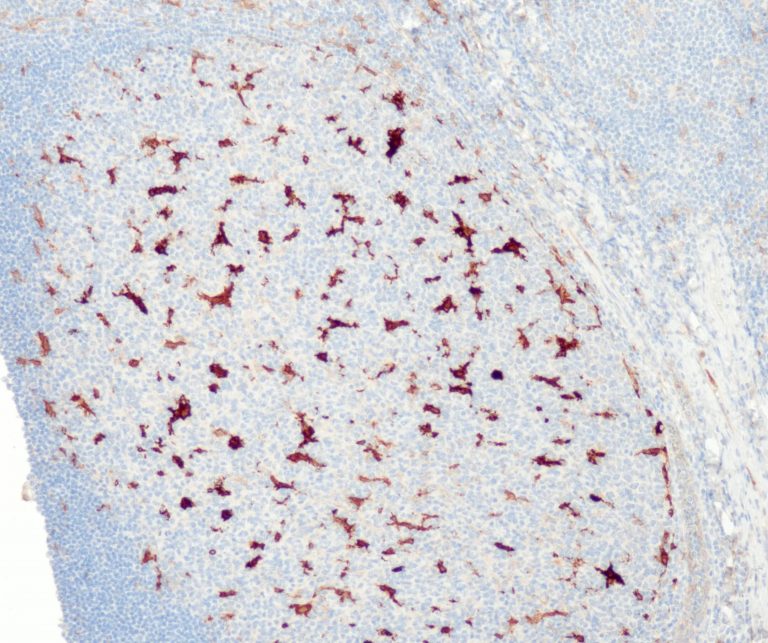

Vascular Pathology

Gastrointestinal (GI) Pathology

General Marker

Breast Pathology

Endocrine Pathology

Gynecological Pathology

Neuropathology

Infection Markers

Lung Pathology

Urinary Tract Pathology

Transplantation Pathology

Soft Tissue Pathology

Hematopathology